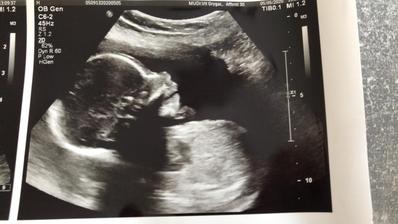

17.3.2020 se miminko ukázalo a je to HOLČIČKA 🥰

7.7.2020 holčička dost jasně potvrzena, 30+5tt váha 1533g, čípek 30mm